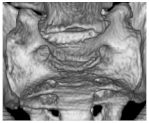

| I | Ia: Unilateral dysplastic transversal process > 19 mm Ib: Bilateral dysplastic transversal process > 19 mm | Ib![]() |

| II | IIa: Unilateral pseudarthrosis between transversal process and sacral bone IIb: Bilateral pseudarthrosis between transversal process and sacral bone | IIa![]() |

| III | IIIa: Unilateral bony union between transversal process and sacral bone IIIb: Bilateral bony union between transversal process and sacral bone | IIIb![]() |

| IV | Unilateral bony union contralateral pseudarthrosis between transversal process and sacral bone | IV![]() |